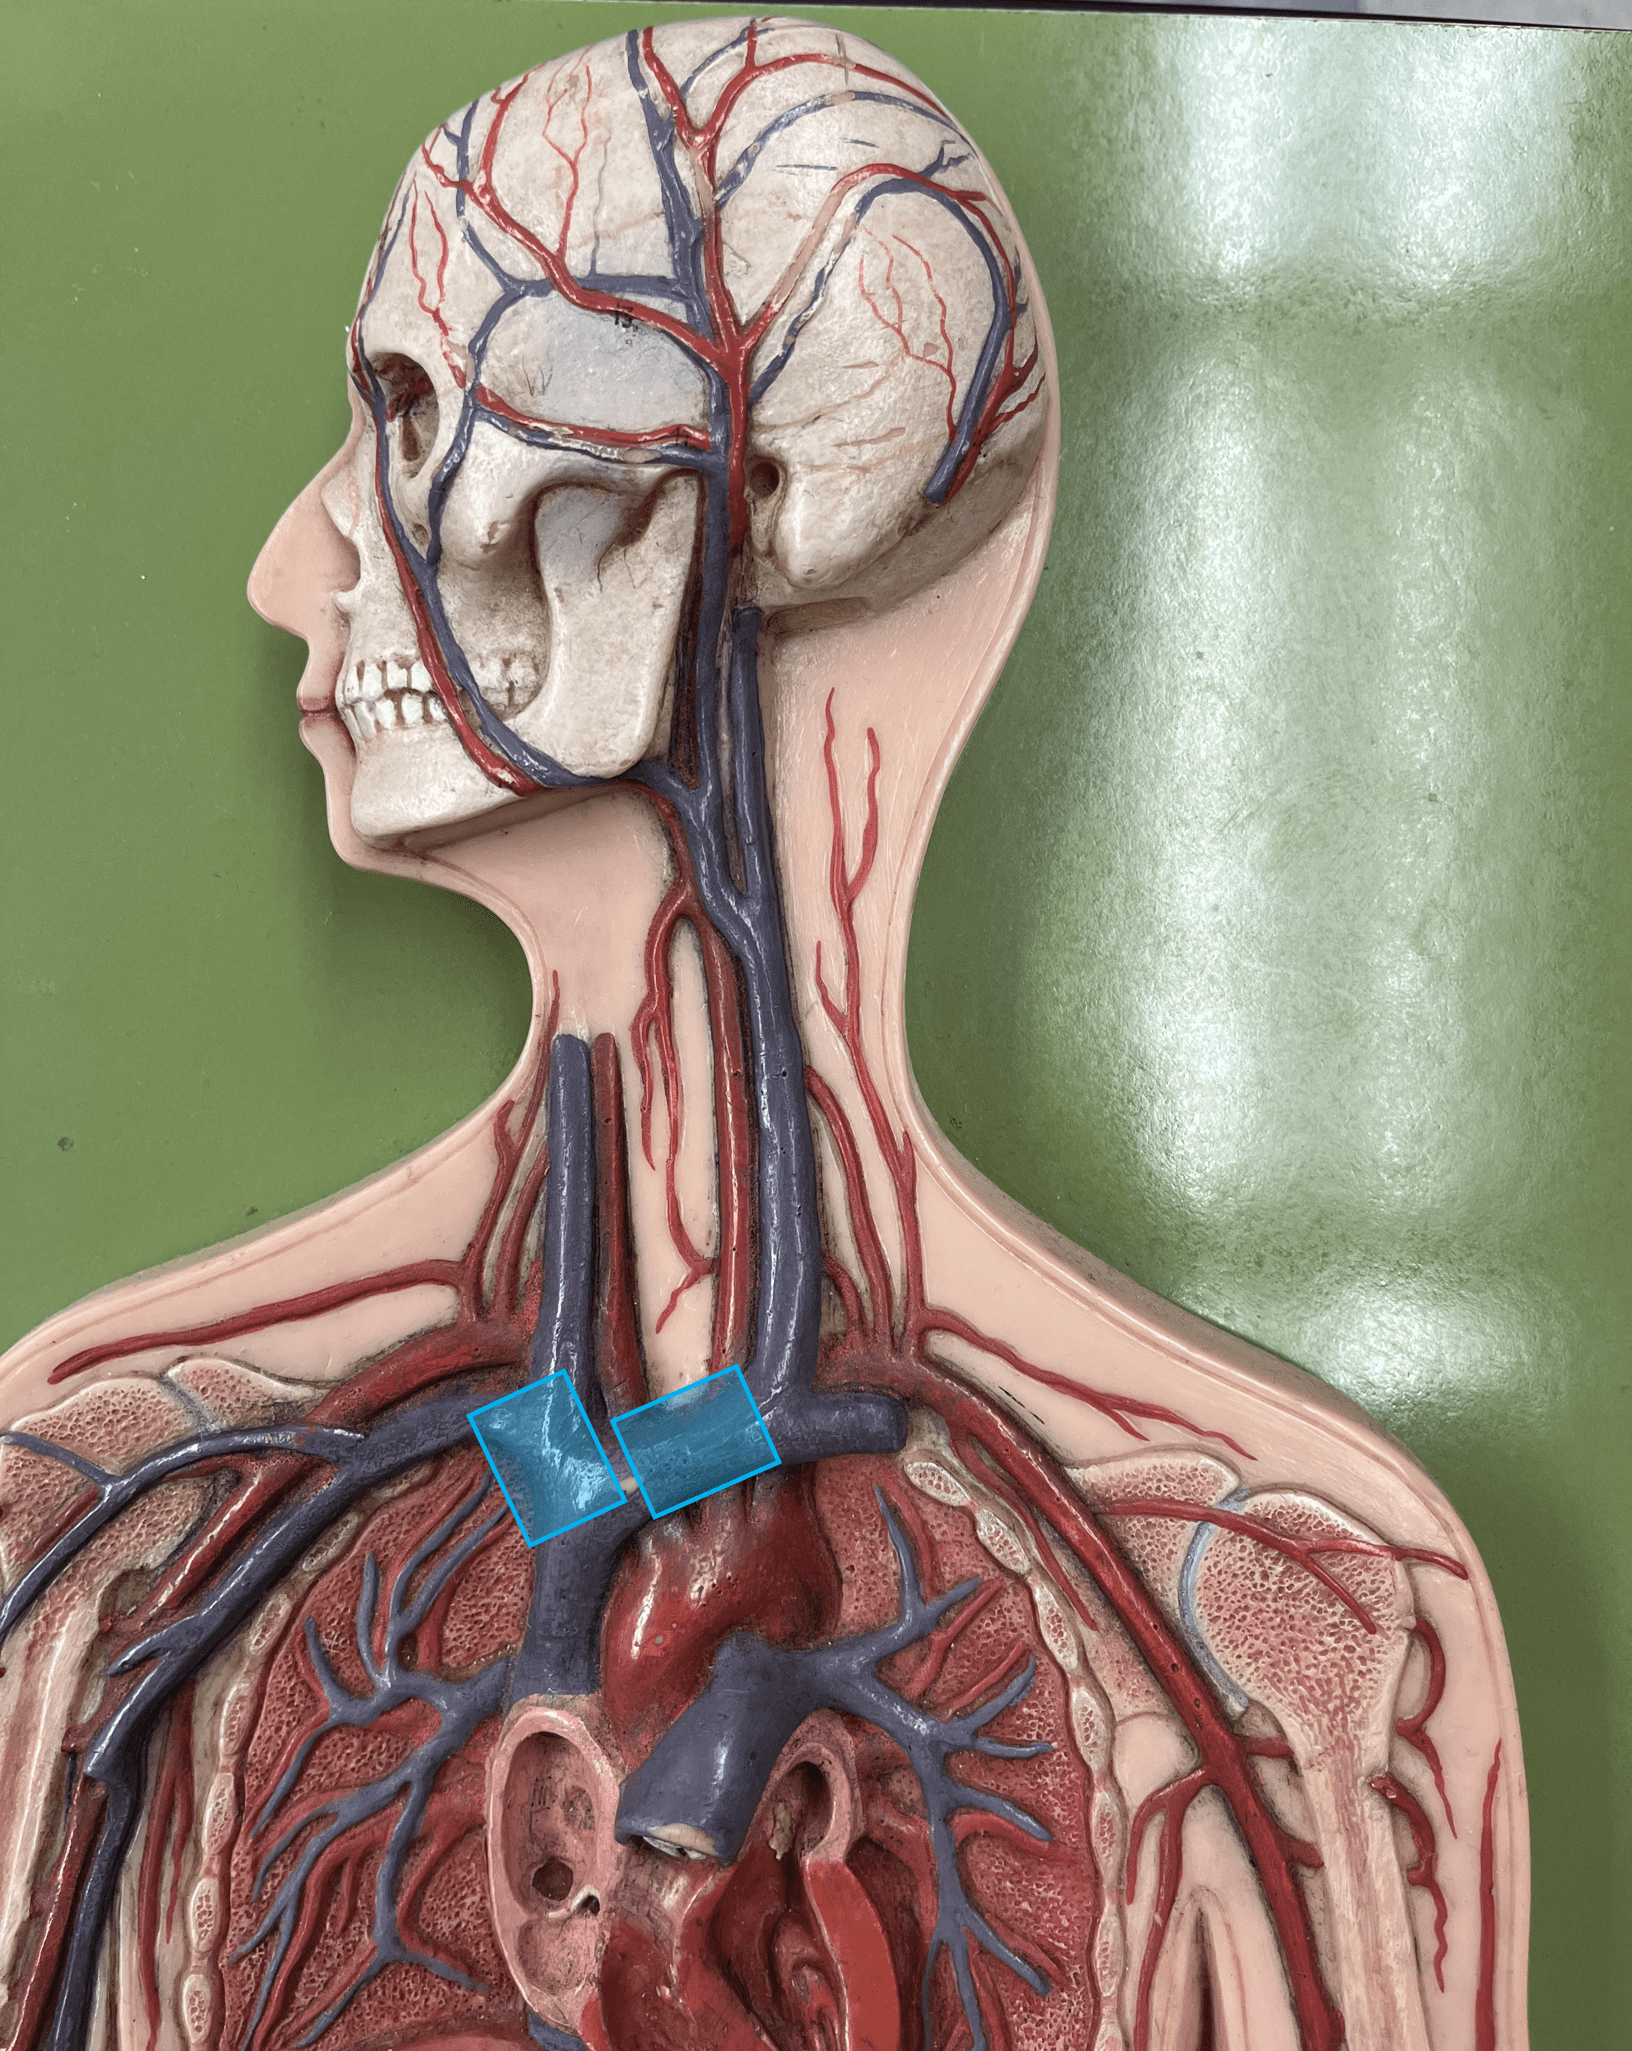

brachiocephalic trunk

• An artery of the thorax.

• Originates from the aortic arch.

• Supplies its branches: the R. subclavian and R. common carotid arteries.

• Originates from the aortic arch.

• Supplies its branches: the R. subclavian and R. common carotid arteries.

aortic arch

• An artery of the thorax.

• Originates as the continuation of the ascending aorta.

• Supplies its branches: the brachiocephalic trunk, L. subclavian artery, and L. common carotid artery.

• Originates as the continuation of the ascending aorta.

• Supplies its branches: the brachiocephalic trunk, L. subclavian artery, and L. common carotid artery.

subclavian artery

• An artery of the thorax.

• Originates from the brachiocephalic trunk (R.) or the aortic arch (L.).

• Supplies its branches.

• Originates from the brachiocephalic trunk (R.) or the aortic arch (L.).

• Supplies its branches.